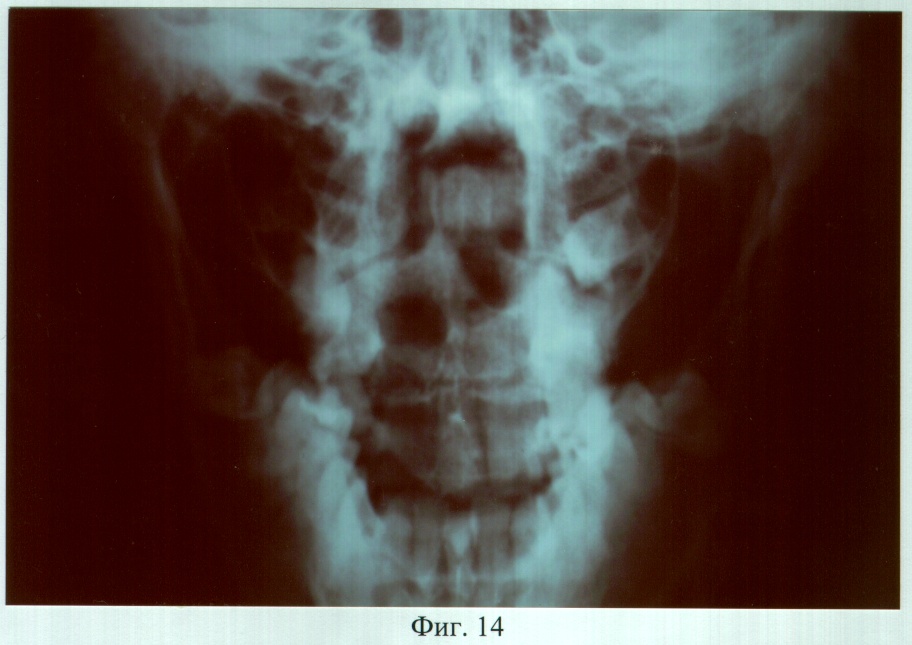

На фиг.14 – рентгенограмма больной С. до ортопедического лечения (прямая проекция).

Пример 2. Больная С., 28 лет, обратилась в клинику ортопедической стоматологии с жалобами на наличие дефекта твердого и мягкого неба, затрудненное пережевывание пищи и попадание ее в полость носа, невнятность, гнусавость речи.

Объективно: нарушение конфигурации лица за счет правосторонней рубцовой деформации и западения мягких тканей верхней губы, крыла носа. В проекции отсутствующих 14, 13, 12 зубов определялся аркообразный дефект альвеолярного отростка правой верхней челюсти. Ротовая полость сообщалась с носовой и носоглоткой посредством четырех дефектов (переднего отдела твердого неба – эллипсовидной формы размером 10×5 мм, среднего отдела твердого неба – округлой формы размером 25×25 мм, заднего отдела твердого неба – эллипсовидной формы размером 10×5 мм, дистальной части мягкого неба – отсутствие язычка, медиальных краев правой и левой передних небно-язычных дужек). Слизистая оболочка, покрывающая костный изъян и прилежащие области, рубцово изменена. Зубная формула: 18, 17, 13, 11, 21, 22, 23, 24, 25, 27, 37, 36, 35, 34, 33, 32, 31, 41, 42, 43, 44, 45, 46, 47. В положении центральной окклюзии нижний зубной ряд сдвинут вперед (прогения), премоляры и моляры нижней челюсти язычными буграми перекрывали щечные бугры премоляров и моляров верхней челюсти, нижние фронтальные зубы располагались впереди верхних. Транспозиция 13 зуба в проекцию отсутствующего 15 зуба с оральной стороны альвеолярного отростка и его тортоанамалия на 80°, вестибулярное расположение 23 зуба.

DS: Операционный дефект твердого и мягкого неба, аркообразный дефект альвеолярного отростка правой верхней челюсти в проекции отсутствующих 14, 13, 12 зубов. Верхнечелюстная микрогнатия, частичная вторичная адентия III класса по Кенеди.

Адаптация к протезу наступила в течение семи дней, после чего больная отмечала удовлетворительное функциональное состояние зубочелюстного аппарата. Фонетическое обследование показало, что до ортопедического лечения нарушено произношение звуков – г, ж, к, п, р, т, ц, ч; k=5; U=21,3%. После протезирования нарушено произношение звуков – г, ж, к, р, ц; k=3; U=6,6%. При осмотре через 3 года больная жалоб не предъявляла, состояние протеза удовлетворительное. Морфологические исследования слизистой оболочки протезного ложа и рентгенография костей лицевого скелета, проведенные до и через 6, 12, 24 и 36 месяцев после протезирования, показали отсутствие признаков воспаления и прогрессирования атрофии.